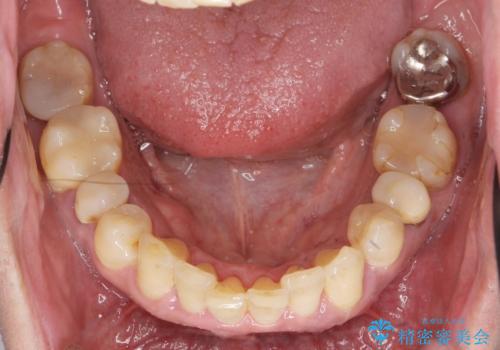

インプラント・ブリッジ補綴を含む、歯周病全顎治療

- 歯が全体的に揺れ始め、恐怖を感じ他院に相談に行ったところ、全体的な歯周病の問題・抜歯の必要性・入れ歯の提案を受け、入れ歯以外の選択肢を希望され来院されました。

全体的な歯周病検査を行い、多数の残すことのできない抜歯の必要な歯を認めたため、残せる歯に対しての徹底的な歯周病治療、失った歯に対しブリッジ・インプラント治療を全顎的に行っていくこととしました。